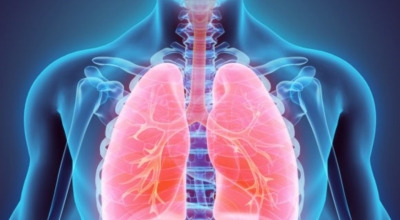

폐암이란?

폐암은 폐에 생기는 악성 종양을 말합니다. 폐에서 직접 발생하는 원발성 폐암과, 다른 장기에서 전이되어 온 전이성 폐암으로 나눌 수 있어요. 전 세계적으로 매년 약 130만 명이 폐암으로 사망하는데, 이는 암으로 인한 사망 원인 중 가장 높은 비중을 차지하고 있습니다.